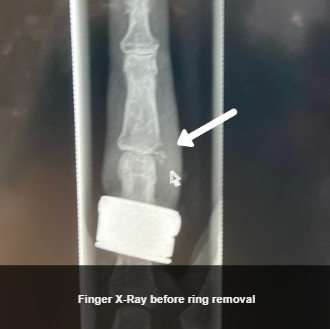

Upon arrival at the second hospital, the patient was assessed and an X-ray was done to further assess the patient’s finger injury before proceeding. There was a minor avulsion fracture noted, but no unstable injury, and the physician discussed with the patient their preferences around different ring removal approaches. The patient was very motivated to try to remove their ring intact, without ring cutting, if at all possible. Based on this, the physician then determined it was reasonable to attempt the Compression Device technique in this unique scenario. Because the physician knew that manipulation of the ring would need to be used for this technique, the physician reapplied a Ring Block.

After finger size was reduced, the physician then used proper ring manipulation techniques and lubrication, and was able to slowly manipulate the ring off of the finger, resulting in the ring being removed intact. A second X-Ray was performed after ring removal, and you can see above that there was no adverse change in the fracture, and the finger did not sustain any bruising or additional swelling and injury, and in fact as you can see in the photo below the finger had significant overall improvement.